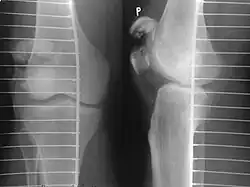

The patella can break in various ways depending on the way it is injured, and into two or more pieces.[1] Types include transverse, with one fracture line and is the most common type,[5] marginal, osteochondral and the rare vertical type, or stellate, where a direct compression force gives rise to a comminuted pattern.[5][7] Patella fractures can be further classified as displaced, where the broken ends of bone do not line up correctly and separate by more than 2mm, or undisplaced and stable where pieces of bone remain in contact with each other.[1][7] If fragments of patella bone stick out from the skin it is known as an open patella fracture, and closed if the overlying skin is intact.[1]

Transverse fracture of patella -

Comminuted fracture of patella -

Osteochondral fracture of patella -

Vertical patella fracture

Some people have a normal two-part patella which can appear as a fracture. The fragment is usually seen in the top outer corner of the patella and can be distinguished from a fracture by being present in both knees.[6]